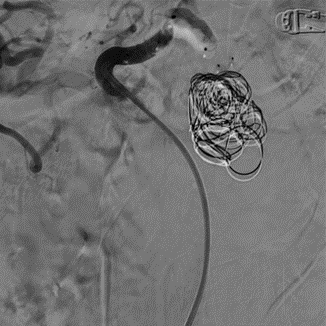

手术过程(三):Ⅳ型AVP直接栓塞载瘤动脉近端,仍有部分侧枝显影

图片

手术过程(四):再于载瘤动脉近端植入一枚Ⅳ型AVP巩固栓塞效果,即时造影显示近端第一枚AVP有血流通过